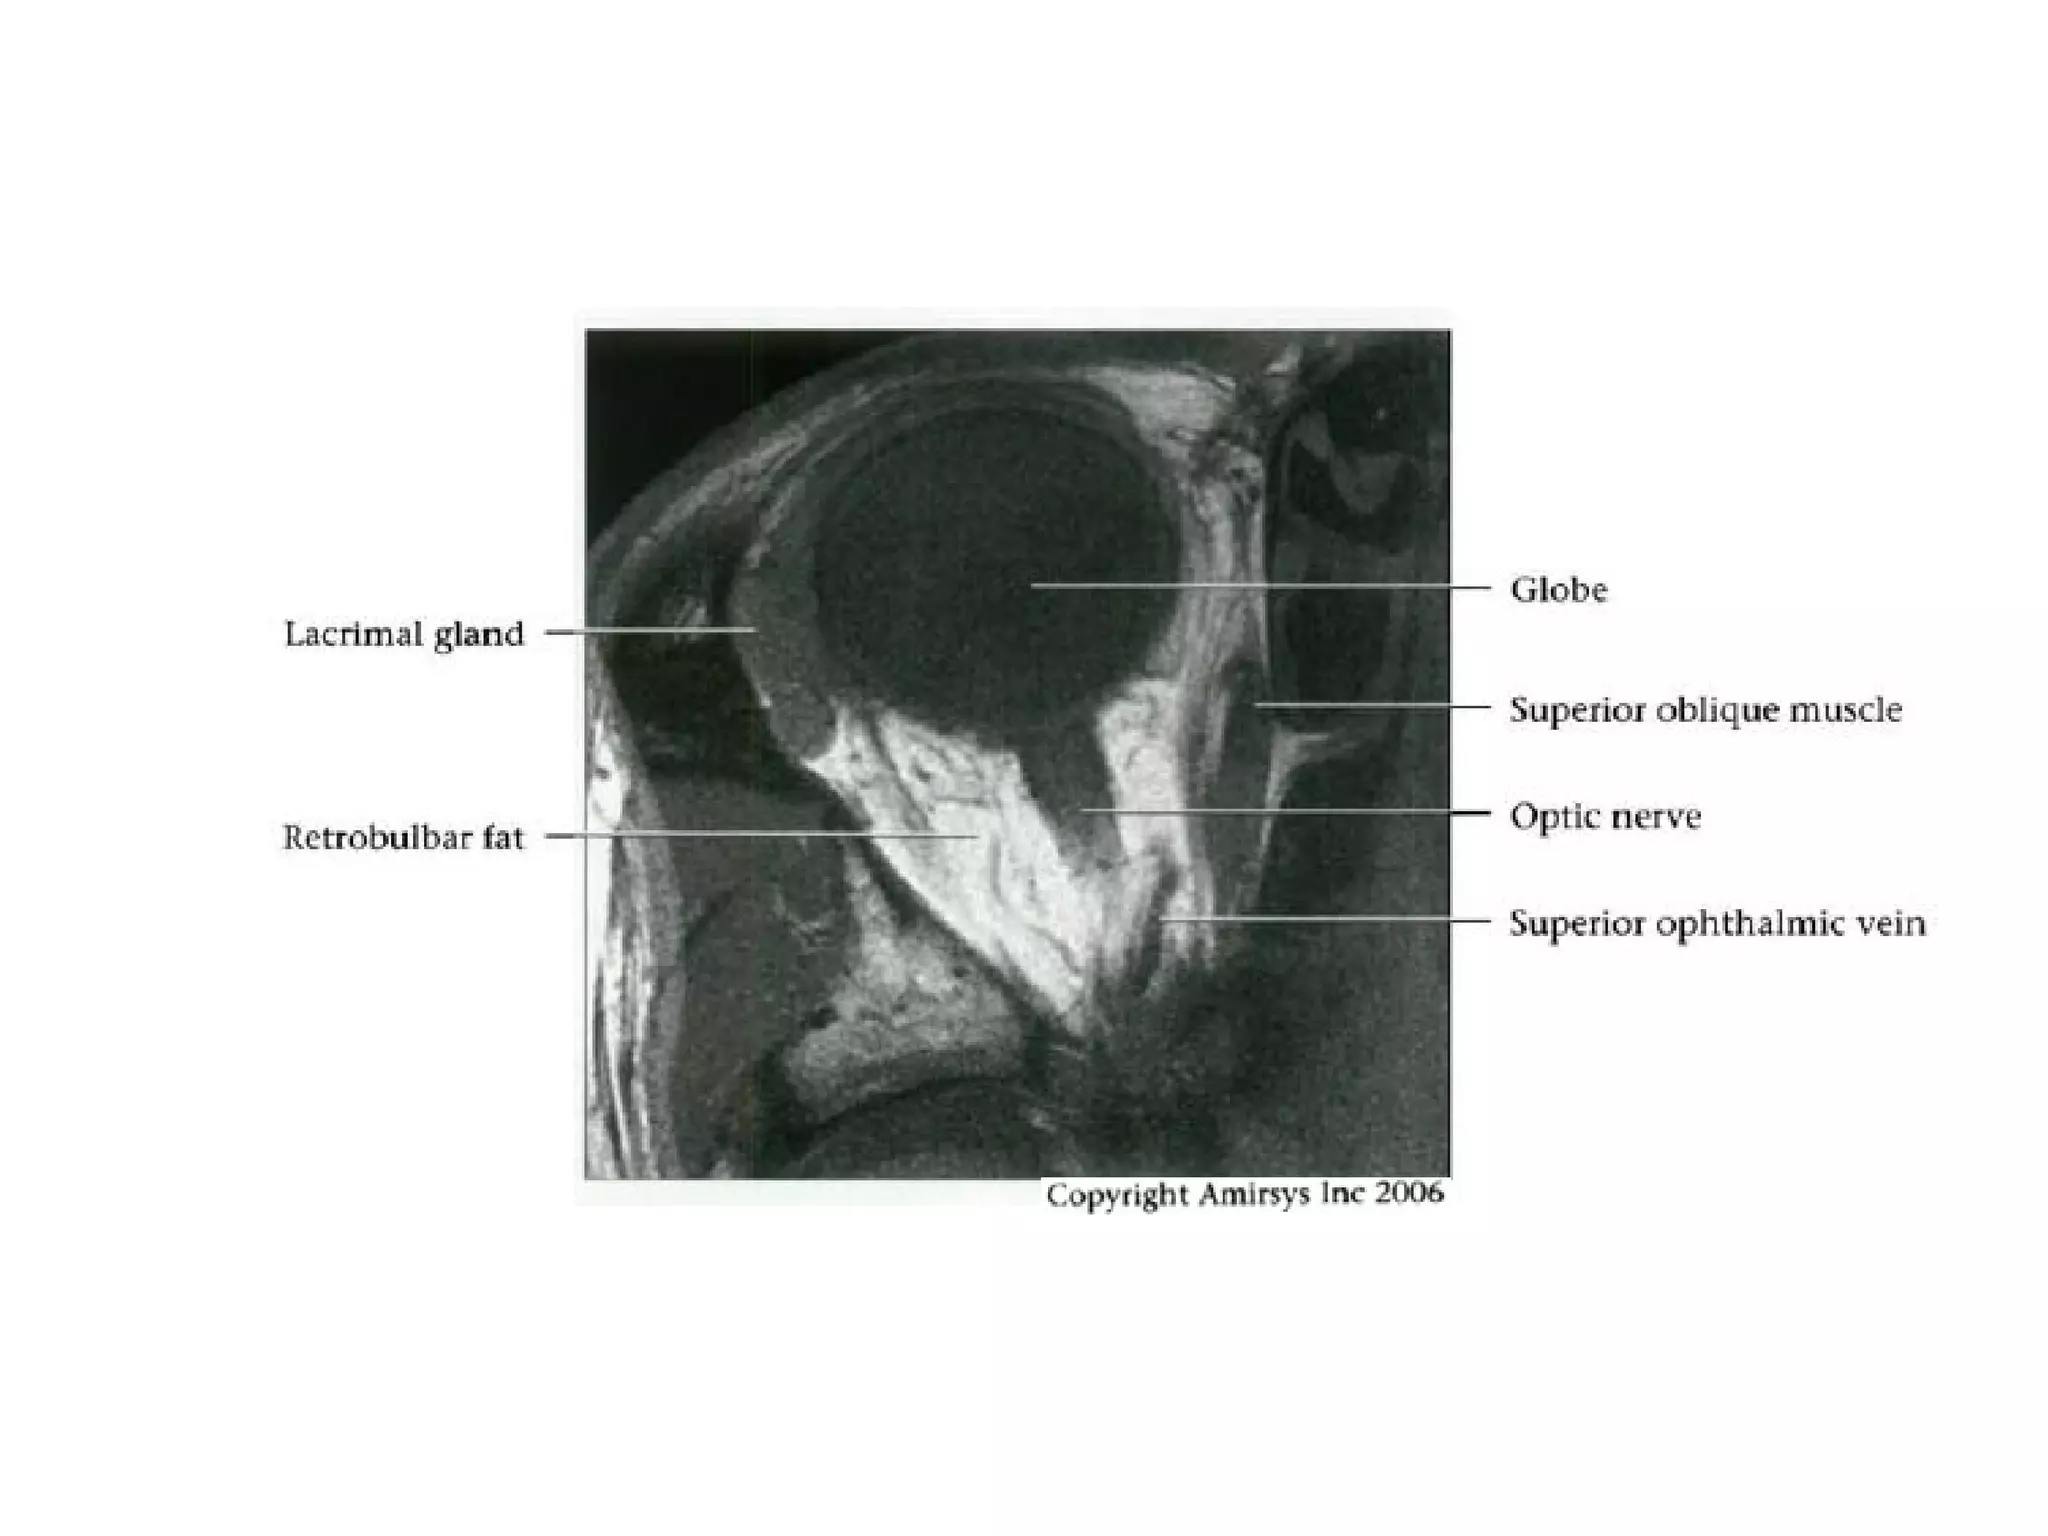

Cranial Nerve II:

The Optic Nerve

• Like the olfactory nerve, the optic nerve is a white-matter tract

without surrounding Schwann cells.

• It includes four anatomic segments: retinal, orbital, canalicular,

and cisternal.

• The retinal segment leaves the ocular globe through the lamina

cribrosa sclerae (the optic foramen of the sclera).

• The orbital segment, which is surrounded by a dural sheath

containing CSF, travels through the center of the fat-filled orbit.

• The canalicular segment is the portion that lies in the optic canal,

below the ophthalmic artery. This segment of the nerve is frequently

overlooked on radiologic images, so it should be specifically sought

when imaging for vision loss.

• Finally, the cisternal segment of the nerve can be visualized in the

suprasellar cistern, where the nerve leads to the optic chiasm. The

anterior cerebral artery passes over the superolateral aspect of the

cisternal segment of the nerve.